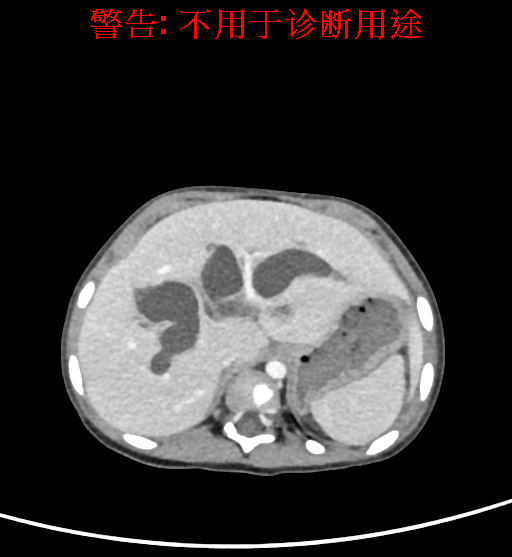

实验室检查: 血常规:血常规:WBC 11.49*109/L,NEU3.60*109/L,RBC4.36*1012/L,HB 119g/L, PLT 411*109/L,MCHC 318.0g/L, PCT 0.45%, RET% 1.64% 生化全套:ALT 18.00 U/L, AST 44.00 U/L, ALT/AST 0.41, ALB 47.35g/L,BIL-T 6.60 umol/L, BIT-D 2.68 umol/L, BUN 4.80 mmol/L, CREA 18.00 umol/L 肝炎全套: 炎症反应标志物: 诊疗过程: CT结果输入海信CAS系统后行3D重建及手术规划后,于2018-6-7全麻下行“胆囊切除+胆总管囊肿切除+肝总管空肠吻合术”手术治疗: 术前三维重建及手术方案设计: 将0.625mm双源薄层CT资料的静脉期和动脉期Dicom格式文件导入海信CAS系统。 通过调节窗宽窗位调整CT序号,对肝实质,胆囊,下腔静脉,肿瘤,肝动脉、门静脉及肝静脉等进行三维重建;系统自动计算肝脏体积,肝脏体积为383.8ml,通过术前模拟手术,精准判断手术切除范围,进行精密术前规划及讨论后实施手术。 手术步骤: 麻醉成功后,患儿取平卧位,2.5%碘伏消毒手术区皮肤,铺无菌巾单。取右上腹纵口长约5m,切开皮肤、皮下织组,腹直肌前鞘、腹直肌,后鞘和腹膜。探查见:胆总管3×2cm大小,胆囊管迂曲,长约10cm。剥离、切除胆囊,游离胆总管,将之横断:①近端即肝总管,剪裁后被吻合用;②远端游离切除囊肿内壁,直至胆总管开口于十二指肠处,冲洗后予以结扎缝扎。距treits韧带20cm处横断空肠:①近端与其远端25cm处的空肠侧壁行端侧双层吻合,吻合口通畅;②远端断端封闭,其侧壁剪开,并经横结肠后提至肝门处,与剪裁的肝总管行端侧双层吻合。缝合修补胆囊床及系膜裂孔,肝门部放置橡胶引流管一根。温盐水冲洗腹腔。检查无活动性出血,清点纱布器械无误,依次缝合腹壁各层。手术顺利,麻醉满意,出血不多,未输血,术后病人先进入麻醉恢复室,苏醒后回病房。手术时术者可开启Hisense CAS系统手势控制功能,对肝脏及胆囊解剖结构进行实时、全方观察、评估,起到术中导航作用。 术后病理: 1. (囊肿壁)囊肿性病变,囊壁构成于增生的纤维组织呈慢性炎,内衬假复层柱状上皮,囊壁内见较多增生的腺体。请结合临床。 2. 慢性胆囊炎。 随访情况: 患儿术后2周恢复良好 术前CT检查:动脉期

平衡期